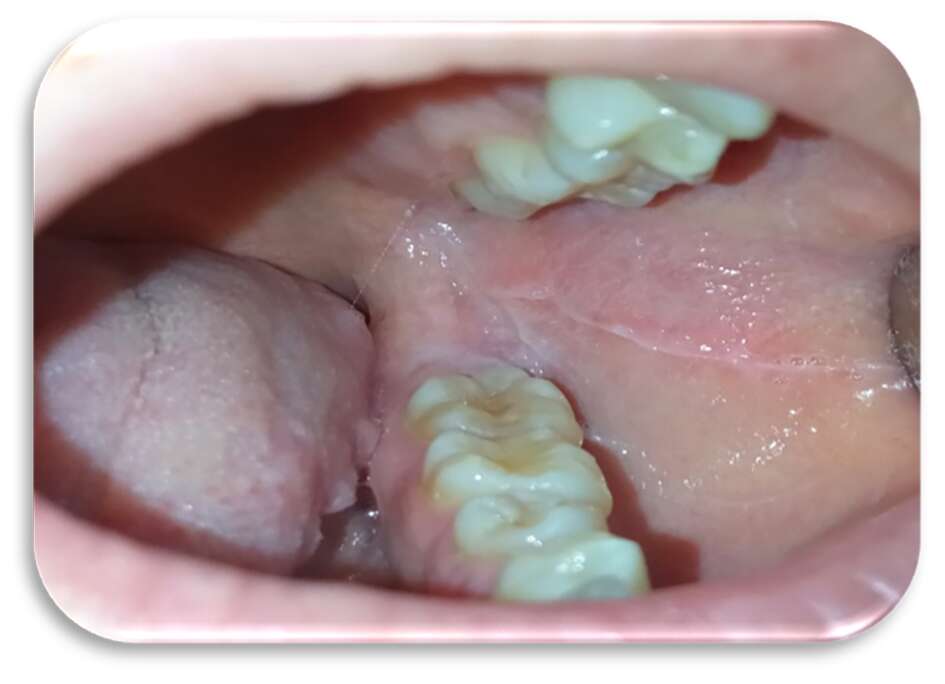

Sia sui margini linguali che sulle mucose geniene erano presenti, inoltre, segni di morsicatio buccarum e linea alba (Figure 3 e 4).

Al quarto giorno di applicazione, la paziente riportava un notevole miglioramento sintomatologico. A sette giorni c’era stata una regressione completa delle lesioni (Figure 5-6), con mucosa integra e normocromatica dove residuava linea alba a livello genieno e linguale (Figure 7-8), per la quale era stato consigliato alla paziente l’uso di un bite inferiore in resina morbida per evitare ulteriori traumi ai tessuti molli.